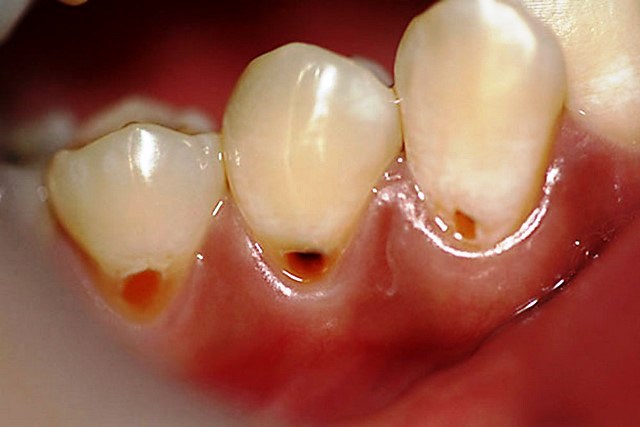

На жевательной поверхности задних зубов, между буграми расположены бороздки и канавки — фиссуры. Фиссуры могут быть узкими и весьма глубокими. Рельеф фиссур индивидуален у каждого из нас, но зубной налет застревает в фиссурах у всех.

Очистить зубной щеткой фиссуры почти невозможно. Бактерии полости рта, перерабатывая налет, образуют кислоту, которая растворяет ткани, образуя кариес. Даже тщательной гигиены рта порой бывает недостаточно. В связи с этим во всем мире в течение 20 лет с успехом используется герметизация фиссур.